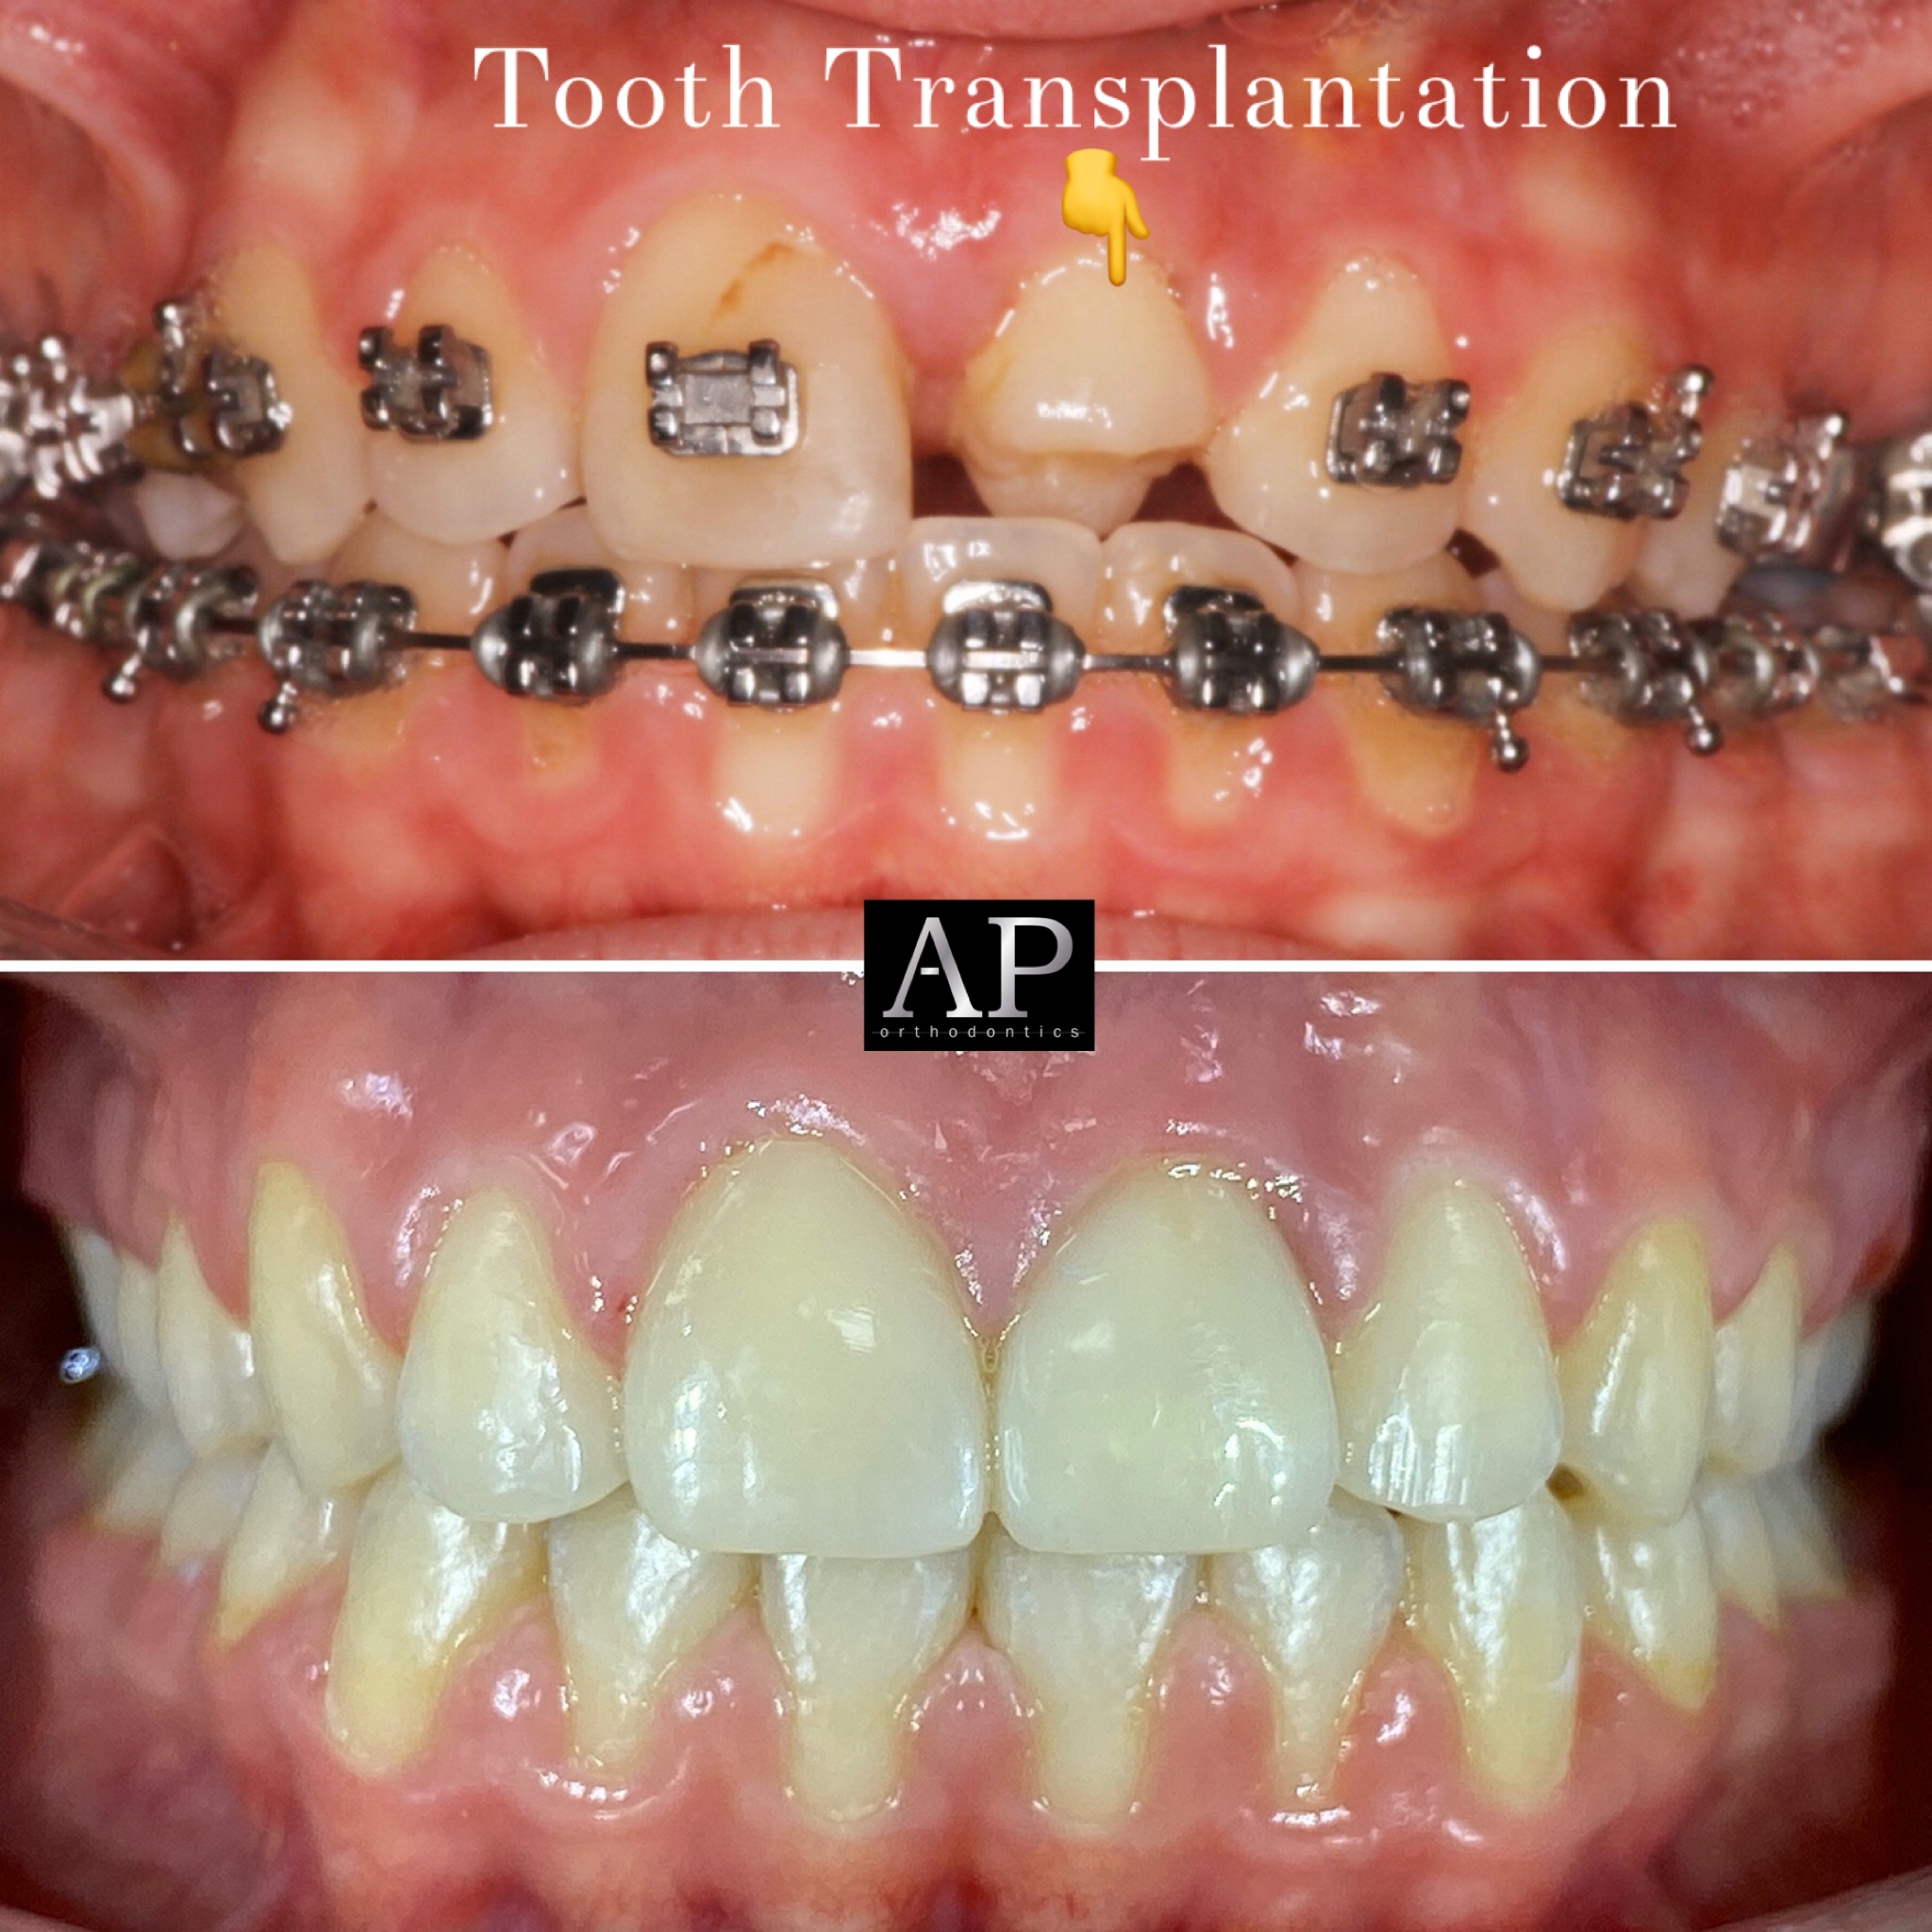

Ορθοδοντικό ιατρείο

Διαφανείς νάρθηκες

Σιδεράκια

Αόρατη ορθοδοντική

Συμβατική ορθοδοντική

Διάφανα σιδεράκια

Σιδεράκια κεραμικά (λευκά)

Ορθοδοντικό ιατρείο

Διαφανείς νάρθηκες

Σιδεράκια

Αόρατη ορθοδοντική

Συμβατική ορθοδοντική

Διάφανα σιδεράκια

Σιδεράκια κεραμικά (λευκά)